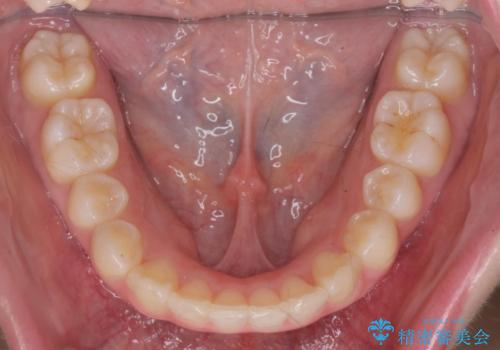

サクソフォン(アルト)の演奏で崩れてしまった歯並び、マウスピース矯正治療

- 高校時代の吹奏楽の部活でサクソフォン(アルト)を担当、「一生懸命練習をしすぎて気づいたら歯並びが悪くなっていた。矯正治療を受けたい!。」

とマウスピース矯正を希望され来院されました。

口腔内の清掃状態の良さに加えて、マウスピースを毎日きっちりと装着し、しっかりと使用していただけたことからワイヤー矯正は行わずにきれいに歯並びを治すことができました。

途中顎位が変わり、マイクロインプラントを併用した上顎臼歯の遠心移動が必要となったため治療が長期化しました。